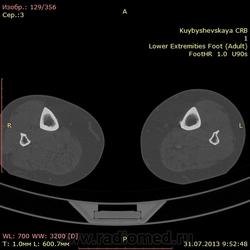

женщина. 69 лет. жалобы на боли в нижней трети голени слева в течении месяца. по снимкам врач написал периостит(к сожалению фотоаппарата нет под рукой)В ближайшее время травм не было. мне досталась только карточка. Пациента не видел. Помогите с диагностикой. вроде бы на зло не похоже. или ошибаюсь?

На зло непохоже, нет мягкоткотканного компонета. Передне-медиальная поверхность голени - самое место для травмы. Только термин "периостит" мне тоже не нравится, написал бы - локальное обызвествления мягких тканей, вероятнее всего посттравматического характера.

По снимкам описал бы как обызвествившуюся гематому, а по КТ больше тянет на экзостоз, только основание очень широкое.